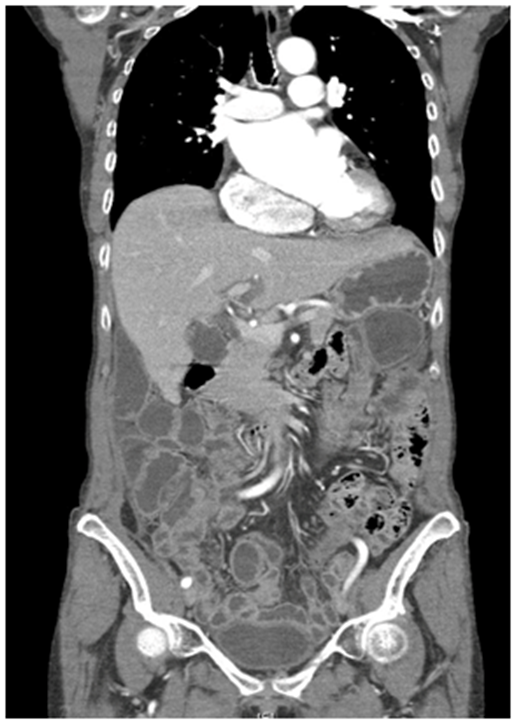

A 70‒year‒old woman was referred by internal medicine, in April 2013, because her physical examination revealed ascites and a mass in the lower abdomen. She had a personal history of cerebrovascular disease and atrial fibrillation. Complementary tests were done to filiate and stage the lesion. Transvaginal ultrasound showed an atrophic utero and enlarged ovaries with low resistance flow and much free fluid within the abdomen. Magnetic resonance imaging showed bilateral carcinoma in the ovaries that together presented dimensions of 11.5x6x7.5 cm (transverse, craniocaudal and anteroposterior), many free fluids and a possible metastatic diaphragmatic nodule. CT scan informed about bilateral pleural effusion and prevascular mediastinal lymph nodes (Figure 1).

Figure 1 CT scan.